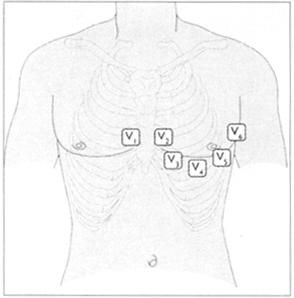

●标准的12导联心电图机一次就能完成。如果用单导联机(一般在病房多见),先记录肢导联,然后逐个记录胸导联。

●肢导一般是水平的,如果不是就用表13所示的彩色电极。最好把电极放在无汗毛的区域,如前臂的内侧和腿的外侧,踝关节之上电极放置的位置见表14和图40。

表14 胸导联的位置

图40 胸导联的位置